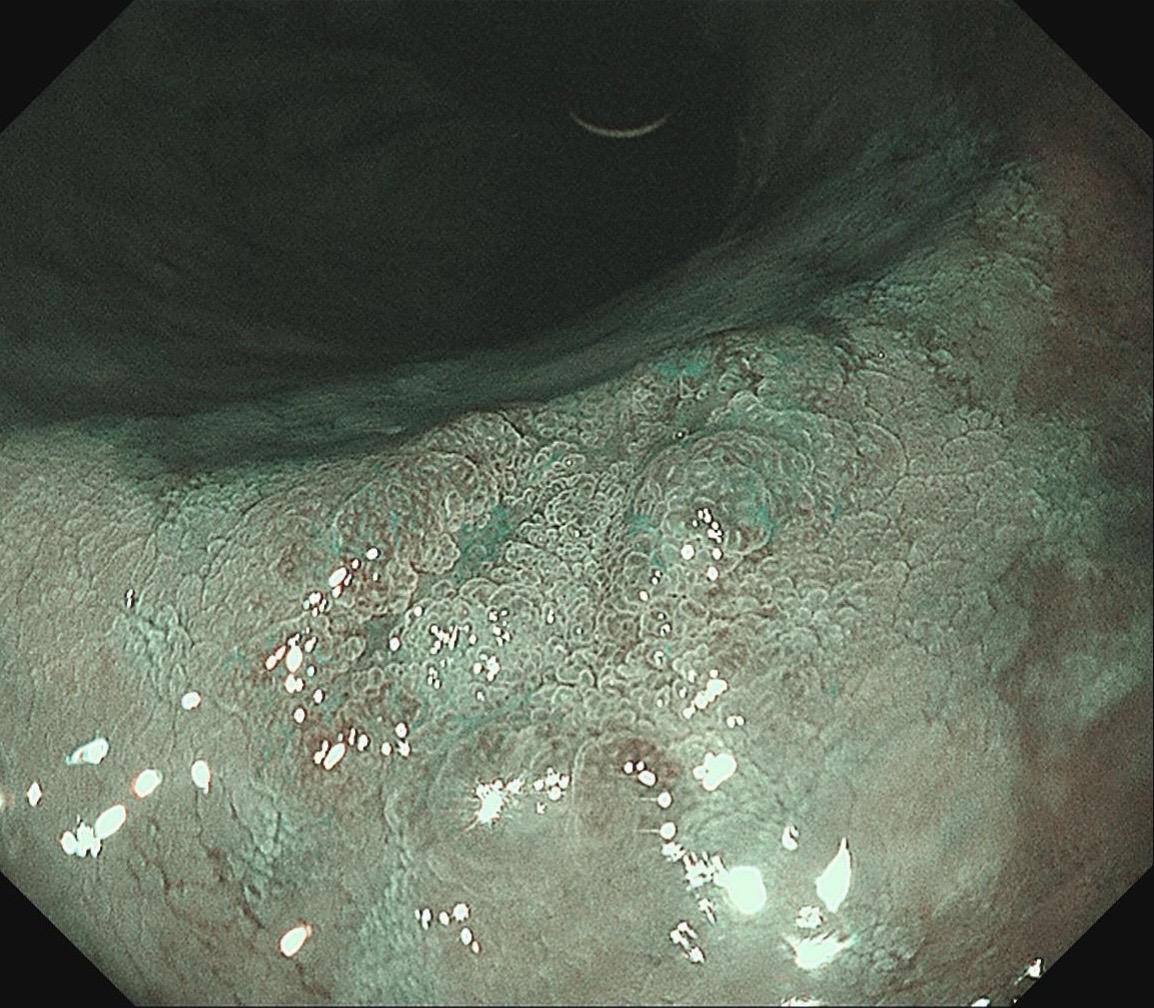

女,57岁,胃角。同事熟人,萎缩背景,色调淡黄,中央浅凹陷,腺管小而密集。